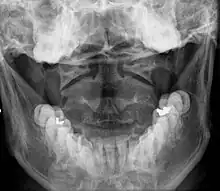

Once there is an onset of the symptoms in the patient, the patients are screened through cervical-spinal imaging techniques: X-ray, CT, MRI. The scanning technique points out any cervical vertebrae defects and misalignments. (Image 1. and 2.) When cervicocranial syndrome is caused as a result of a genetic disease, then family history and genetic testing aid in making an accurate diagnosis of cervicocranial syndrome.